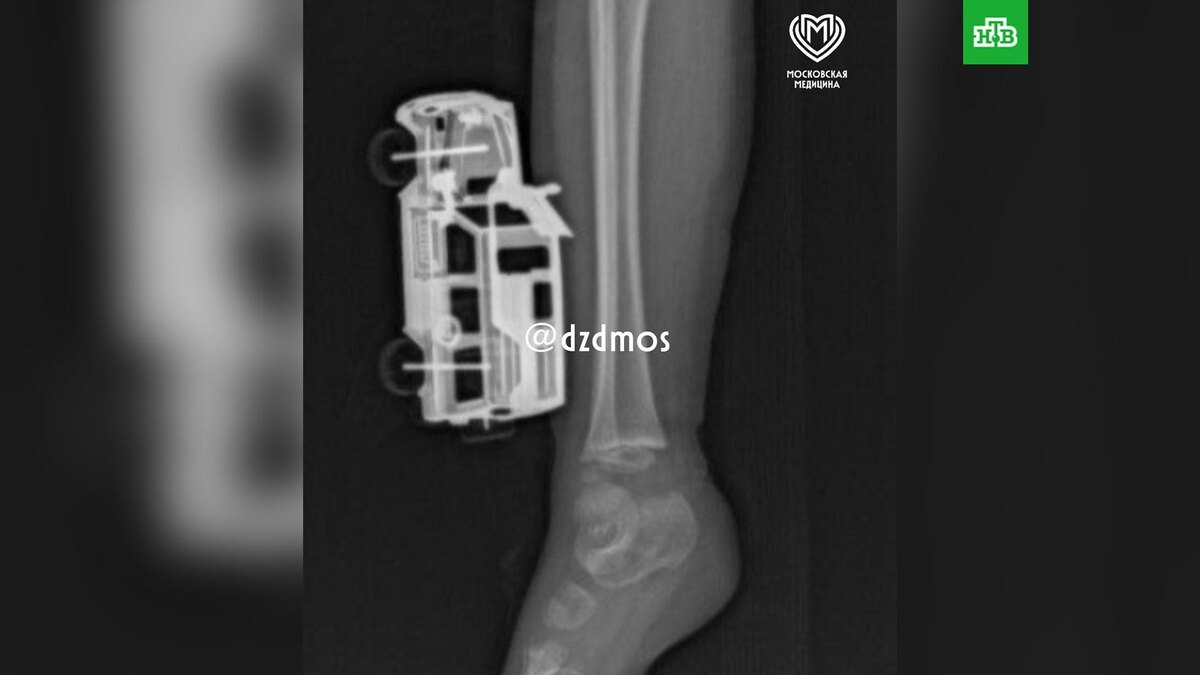

В Москве ребенок спрыгнул с кровати и упал на металлическую машинку. Игрушка глубоко вошла в ногу, повредив мягкие ткани голени. Родители вызвали скорую помощь, и мальчика привезли в больницу Сперанского.

Магомед Шихахмедов, травматолог-ортопед отделения экстренной хирургической помощи: «Маленькому пациенту сделали рентгенографию, чтобы исключить повреждения костей голени и понять глубину повреждения. Затем удалили игрушку и выполнили хирургическую обработку серьезной раны».

Через сутки после операции ребенка выписали домой. Пока он остается под амбулаторным наблюдением.